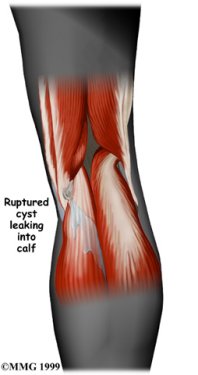

Sometimes a cyst will suddenly burst underneath the skin, causing pain and swelling in the calf. A ruptured popliteal cyst gives symptoms just like those of a blood clot in the leg, called thrombophlebitis. For this reason, it is important to determine right away the cause of the pain and swelling in the calf. Once the cyst ruptures, the fluid inside the cyst simply leaks into the calf and is absorbed by the body. In this case, you will no longer be able to see or feel the cyst. However, the cyst will probably return in a short time.

Ruptured Cyst